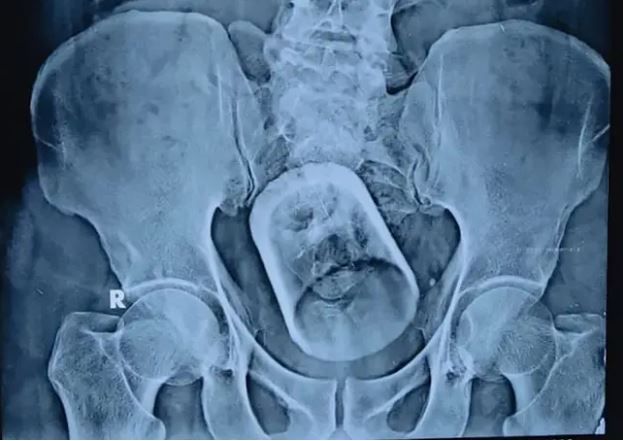

Da staunten die Ärzte nicht schlecht, als das Röntgenbild den Grund für die Beschwerden des Patienten zeigte.